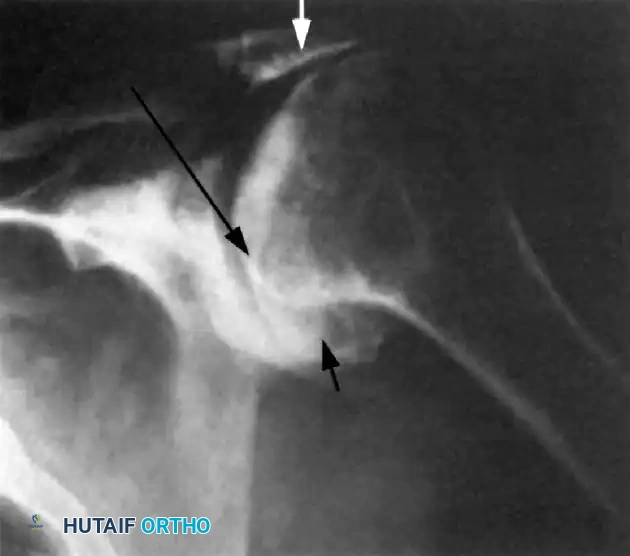

Associated Surgical & Radiographic Imaging